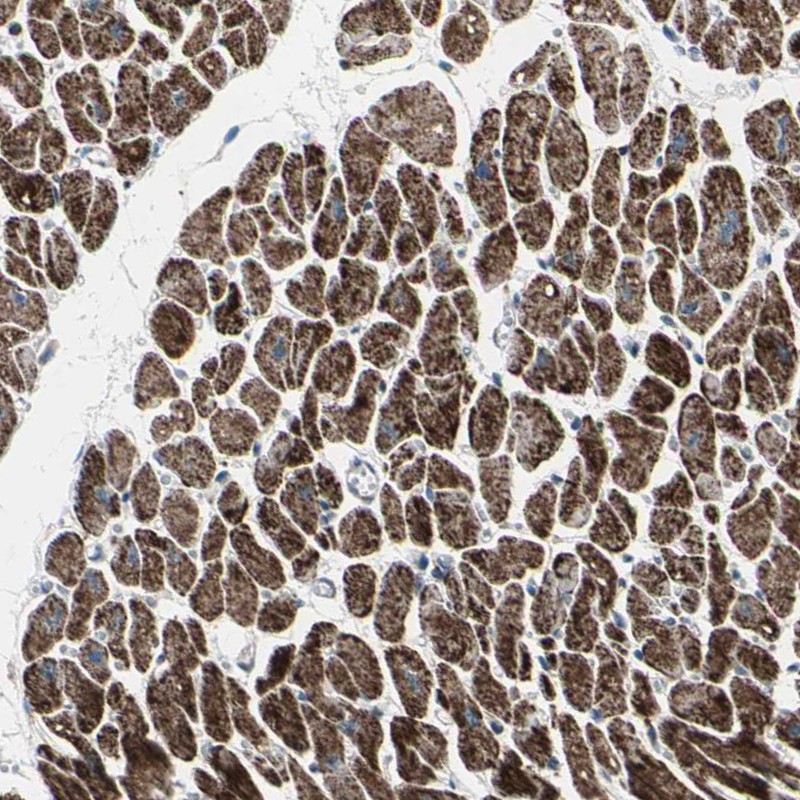

Immunohistochemistry analysis in human heart muscle and pancreas tissues using Anti-UQCRC2 antibody. Corresponding UQCRC2 RNA-seq data are presented for the same tissues.